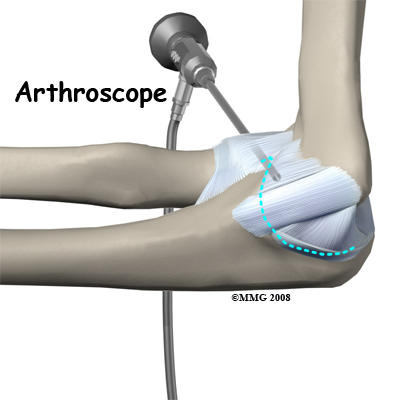

Magnetic resonance imaging (MRI) with contrast dye is used to diagnose ligamentous rupture. The test doesn't always show a problem when there is one. This is called a false-negative result. Ultrasound and CT scans may be helpful. Some surgeons prefer to use arthroscopy to make the final diagnosis. The presence and severity of valgus gapping can be confirmed. Studies using these more advanced test methods to diagnose UCL injuries are being done. More data is needed before they become routine in the diagnosis of UCL injuries.

Surgery

When the condition fails to respond to conservative care described above, surgery may be indicated. If pain is the primary symptom and there is no evidence that the elbow joint is grossly unstable, the surgeon may use an (a tiny fiber-optic TV camera) to look inside the elbow and see the condition of the joint and the soft tissues. It may be possible to debride any tissue fragments or frayed edges. During debridement, the surgeon carefully cleans the area by removing any dead or damaged tissue. Any bone spurs or areas of calcium build-up are also removed.